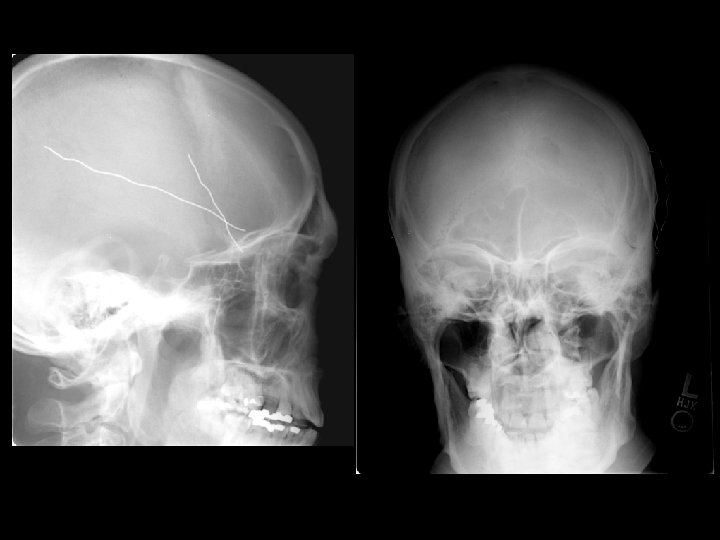

Skull Fracture • Multiple types: – Linear, depressed, and basilar • CT must be viewed on bone windows • Most important feature is injury occurring to the brain at the site of the skull fracture • Linear skull fracture: – If closed, can simply be observed

Skull Fracture • Basilar skull fracture: – Most often involving the temporal bone – Clinical diagnosis (CT often fails to show fracture) • Raccoon’s (Panda’s) eyes, hemotympanum, Battle’s sign (mastoid ecchymosis), CSF rhinorrhea • Depressed skull fracture: – Surgical elevation: • if greater than width of skull or • > 5 mm